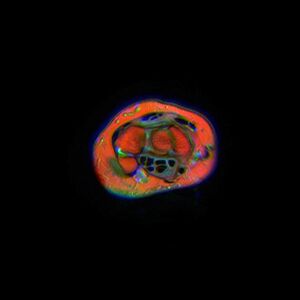

The narrowest section of the tunnel is located a centimetre beyond the mid-line of the distal row of carpal bones where the sectional area is limited to 1.6 cm2.[2]

Movements in the wrist affect the shape and width of the carpal tunnel. The width decreases considerably during normal range of motion in the wrist and because the carpal bones move in relation to each other with every motion of the hand the bony walls of the tunnel are not rigid. Both flexion and extension increase compression in the carpal tunnel.

- Flexing the wrist causes the flexor retinaculum to move closer to the radius which considerably decreases the cross section of the proximal opening of the tunnel. Additionally, the distal end of the capitate presses into the opening.

- In extreme extension, the lunate constricts the passage as it is pressed toward the interior of the tunnel.[1]